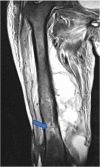

We present a case series comprising three patients with concomitant septic arthritis of the knee and osteomyelitis of the femur. Early advanced imaging rendered the accurate diagnosis of the condition and the appropriate surgical approach and technique used to treat the infection. Repeated extensive surgical debridement, irrigation and insertion of antibiotic-impregnated cement rod into the femur were required, in addition to long term antibiotics. The infection in all three cases was eradicated successfully. Following a period of physical rehabilitation, they had fairly preserved independent ambulatory function. We advocate a high index of suspicion of this condition with subsequent early advanced imaging for a timely diagnosis. In addition, we described our challenges in the fabrication process of the antibiotic-impregnated cement rod.